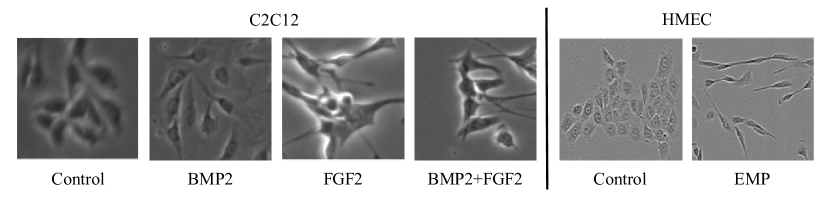

Refer to caption

Fig. 8: Cell images on all conditions in all datasets. The left side is the C2C12 dataset, and the right side is the HMEC datset. The appearance of cells are significantly different among the culture conditions.

C2C12: This is open-source dataset [26] consisting of myoblast cells captured by phase-contrast microscopy at a resolution of 1040×1392104013921040\times 1392 pixels and cultured under four different conditions; 1) Control (no growth factor), 2) FGF2 (fibroblast growth factor), 3) BMP2 (bone morphogenetic protein), 4) BMP2+FGF2 (fibroblast growth factor + bone morphogenetic protein). As shown in Fig. 8, the cell appearances differ between conditions. For example, the cells in FGF2 are extremely elongated or shrunken, and they severely touch, while the ones in BMP2 are much larger than those in Control. We separated patches of 128×128128128128\times 128 pixels from the full images of the datasets. The ground truth was given to only 24 patches (approximately a quarter of one entire image) in each condition. In the evaluation of domain adaptation experiments, we used one sequence as unlabeled data (100 entire images) and the other sequence as test data (100 entire images) under different conditions from the training data. In the evaluation of the same domain experiments, we used one sequence as unlabeled data (100 entire images) and the other sequence as test data (100 entire images) under the same conditions from the training data. Note that we did not use validation samples to tune hyper-parameters because of the protocol of unsupervised domain adaptation.

HMEC: This dataset contains images of human mammary epithelial cells (HMEC) captured by phase-contrast microscopy at a resolution of 1272×95212729521272\times 952 and cultured under two conditions; 1) Control (no stimulus) and 2) EMT (epithelial-mesenchymal transition) [35]. Example images for each condition are shown in Fig. 8, where the appearance of the cells in Control are round and those in EMP2 are elongated. In the evaluation of all experiments, we used the same setting with C2C12.